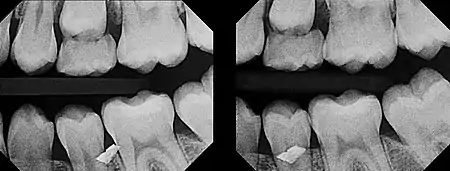

In 1909, Clark described a radiographic procedure for localizing impacted teeth to determining their relative antero-posterior position.[1] If the two teeth (or, by extension, any two objects, such as a tooth and a foreign object) are located in front of one another relative to the x-ray beam, they will appear superimposed on one another on a dental radiograph, but it will be impossible to know which one is in front of the other. To determine which is in front and which is behind, Clark proposed his SLOB rule, as a complicated set of three radiographs, but which can be simplified as follows using just two:

- Expose another film while angle of the x-ray beam has been changed. If an object moves in the same direction as the source of the x-ray beam, it is lingual to the other object. If the object moves in the opposite direction of the source, it is buccal to the other object.

- Same Lingual; Opposite Buccal

In 1952, Richards amended this rule using only 2 radiographs,[2][3] asserting that the object positioned more buccally will move more relative to the object positioned more palatally or lingually.

As a generalization, but not specifically stated as part of Richards' buccal object rule, the more buccal an object is (i.e. the closer it is to the x-ray source) the more it will move in the second radiograph when repositioning the x-ray source.